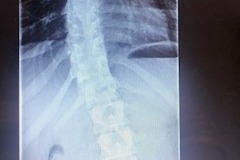

Rhiannas spine – the twisting will get more severe if not treated